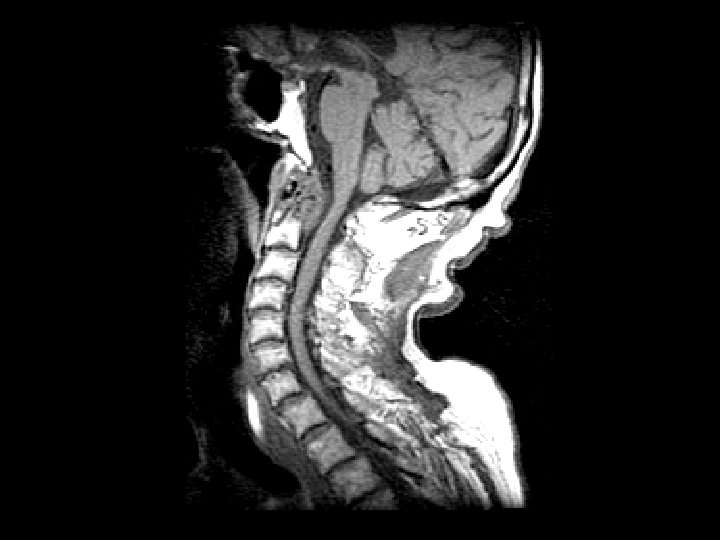

Rheumatoid arthritis • Findings: – Destruction of the dens and the anterior C 1 arch by a soft tissue mass – Impression of the anterior thecal sac with slight deformation of the cervical cord • ddx: – Infection – Metastasis